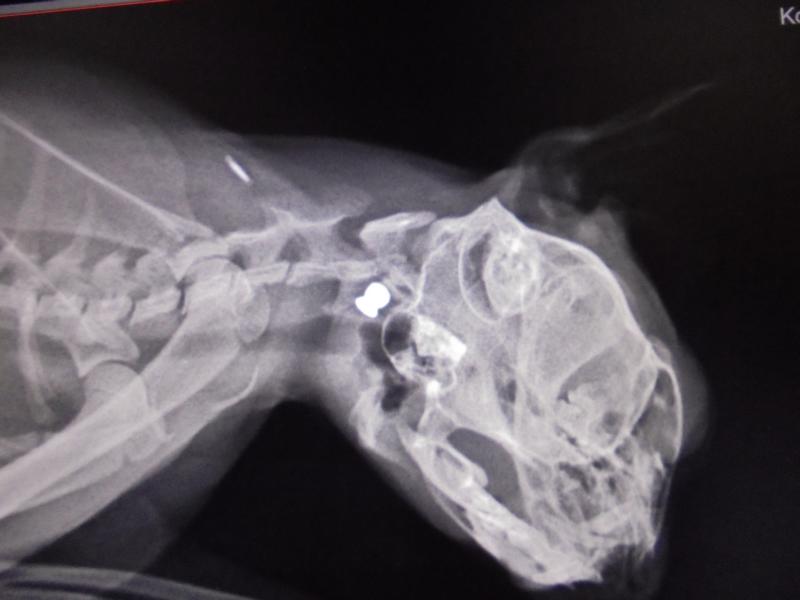

Einen großen Schreck bekamen wir, als sich die Beule am Hals einer Jungkatze als Diabolo - einem Geschoss - entpuppte (s. Fotostrecke). Es ist wirklich nicht zu fassen.